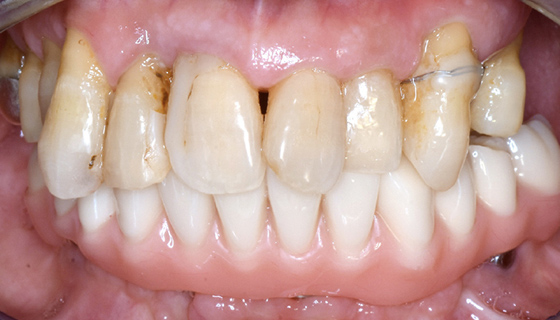

最終補綴物装着

下顎の歯がしっかりと固定され、きちんと噛めるようになりました。